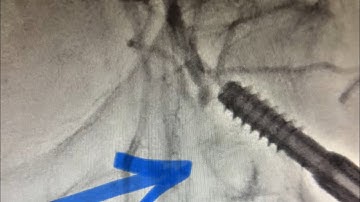

SFA CTO Revascularization with Concurrent BTK CTO